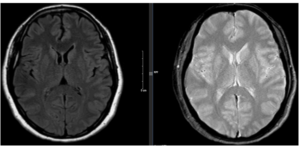

CA LÂM SÀNG: ĐIỀU TRỊ UNG THƯ PHỔI BIỂU MÔ TUYẾN DI CĂN XƯƠNG

CA LÂM SÀNG: ĐIỀU TRỊ UNG THƯ PHỔI BIỂU MÔ TUYẾN DI CĂN XƯƠNG GS. TS. Mai Trọng Khoa – PGS. TS. Phạm Cẩm Phương – PGS. TS. Phạm Văn Thái – ThS. Hoàng Công Tùng – SV Lê Đình Minh Hiếu Đặt vấn đề: Ung thư phổi...